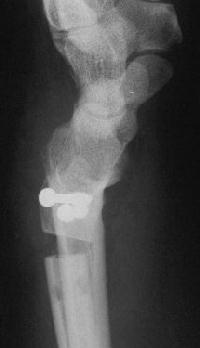

Case 3. Adult bilateral congenital Madelung's deformity with pain and extensor tendinitis, treated with the Sauve Kapandji (Lauenstein) procedure: segmental distal ulnar ostectomy and distal radioulnar joint fusion.

The right side, preop:

And postop: Here, an inadequate ulnar gap led to heterotopic bone formation which almost resulted in a pseudarthrosis.